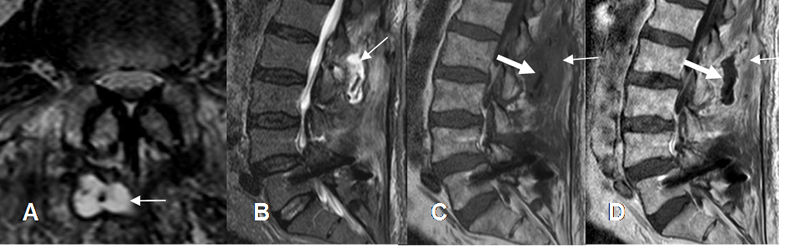

Fig 130. Infección postQx.

A: RM axial y B: RM sagital en T2. Cambios postQx, con colección hiperintensa en los tejidos blandos.

C: RM sagital en T1 y D: RM sagital en T1 con contraste. Cambios inflamatorios de tejidos blandos, hipointensos y que realzan con el contraste (Flecha delgada). La colección no realza y corresponde a absceso. (Flecha gruesa).